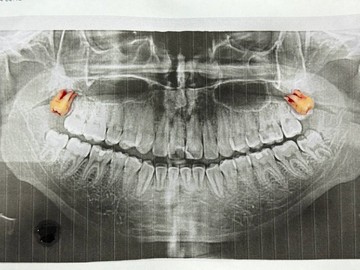

Атравматичное удаление зубов – наиболее безболезненная и щадящая процедура, которая практически не травмирует десну и костную ткань.

Зуб извлекается частями, что позволяет не травмировать окружающие ткани.

В нашей клинике осуществляется удаление самых сложных «зубов мудрости». Обычно удаление зуба под местной анестезией занимает от 10-15 минут, но иногда процедура может занять 30 или даже 60 минут и более.